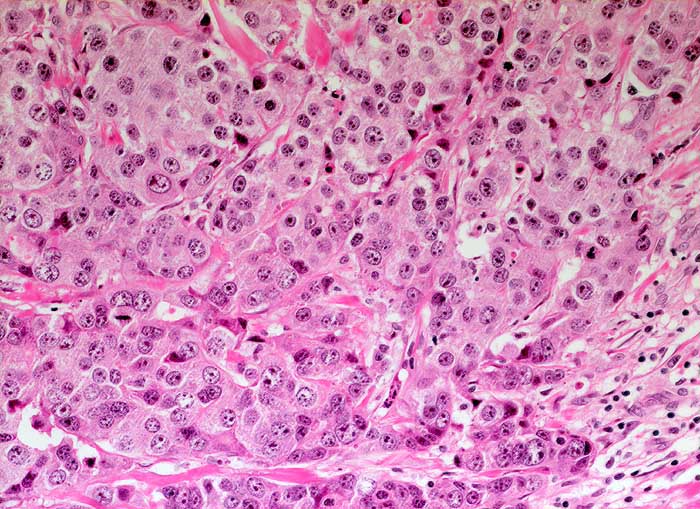

PathoPic ID 5594 - Wenig differenziertes invasiv duktales Mammakarzinom

Wenig differenziertes invasiv duktales Mammakarzinom

Trabekulär angeordnete stark atypische Tumorzellen mit deutlicher Pleomorphie und hyperchromatischen Kernen. Reichlich eosinophiles Zytoplasma.

Sonographisch wachsender Befund unklarer Dignität im oberen äusseren Quadranten rechts.

Histologie

200